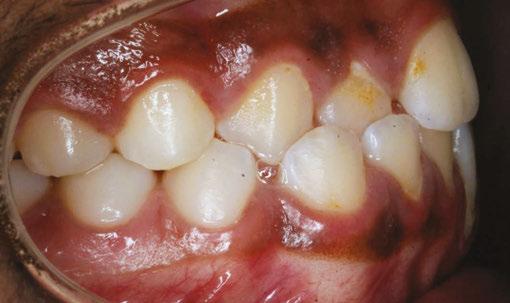

Figures 2A and 2B: Open bite corrected with myofunctional therapy. 2A. Pre-myofunctional therapy: This patient was in braces for 3 years with no success at closing the open bite. 2B. Post-myofunctional therapy: After 5 months of myofunctional therapy to address the mouth breathing and tongue thrust, the open bite closed

Figures 3A and 3B: 3A. Pre-myofunctional therapy: Anterior open bite caused of soft tissue dysfunction including incorrect lingual rest posture and tongue thrust. 3B. Post-myofunctional therapy: 4 years after the start of myofunctional therapy with no orthodontic treatment, and the open bite closed. By taking the tongue pressure off of the teeth in OMT, the occlusion was able to normalize. The orthodontist feels the patient does not need braces